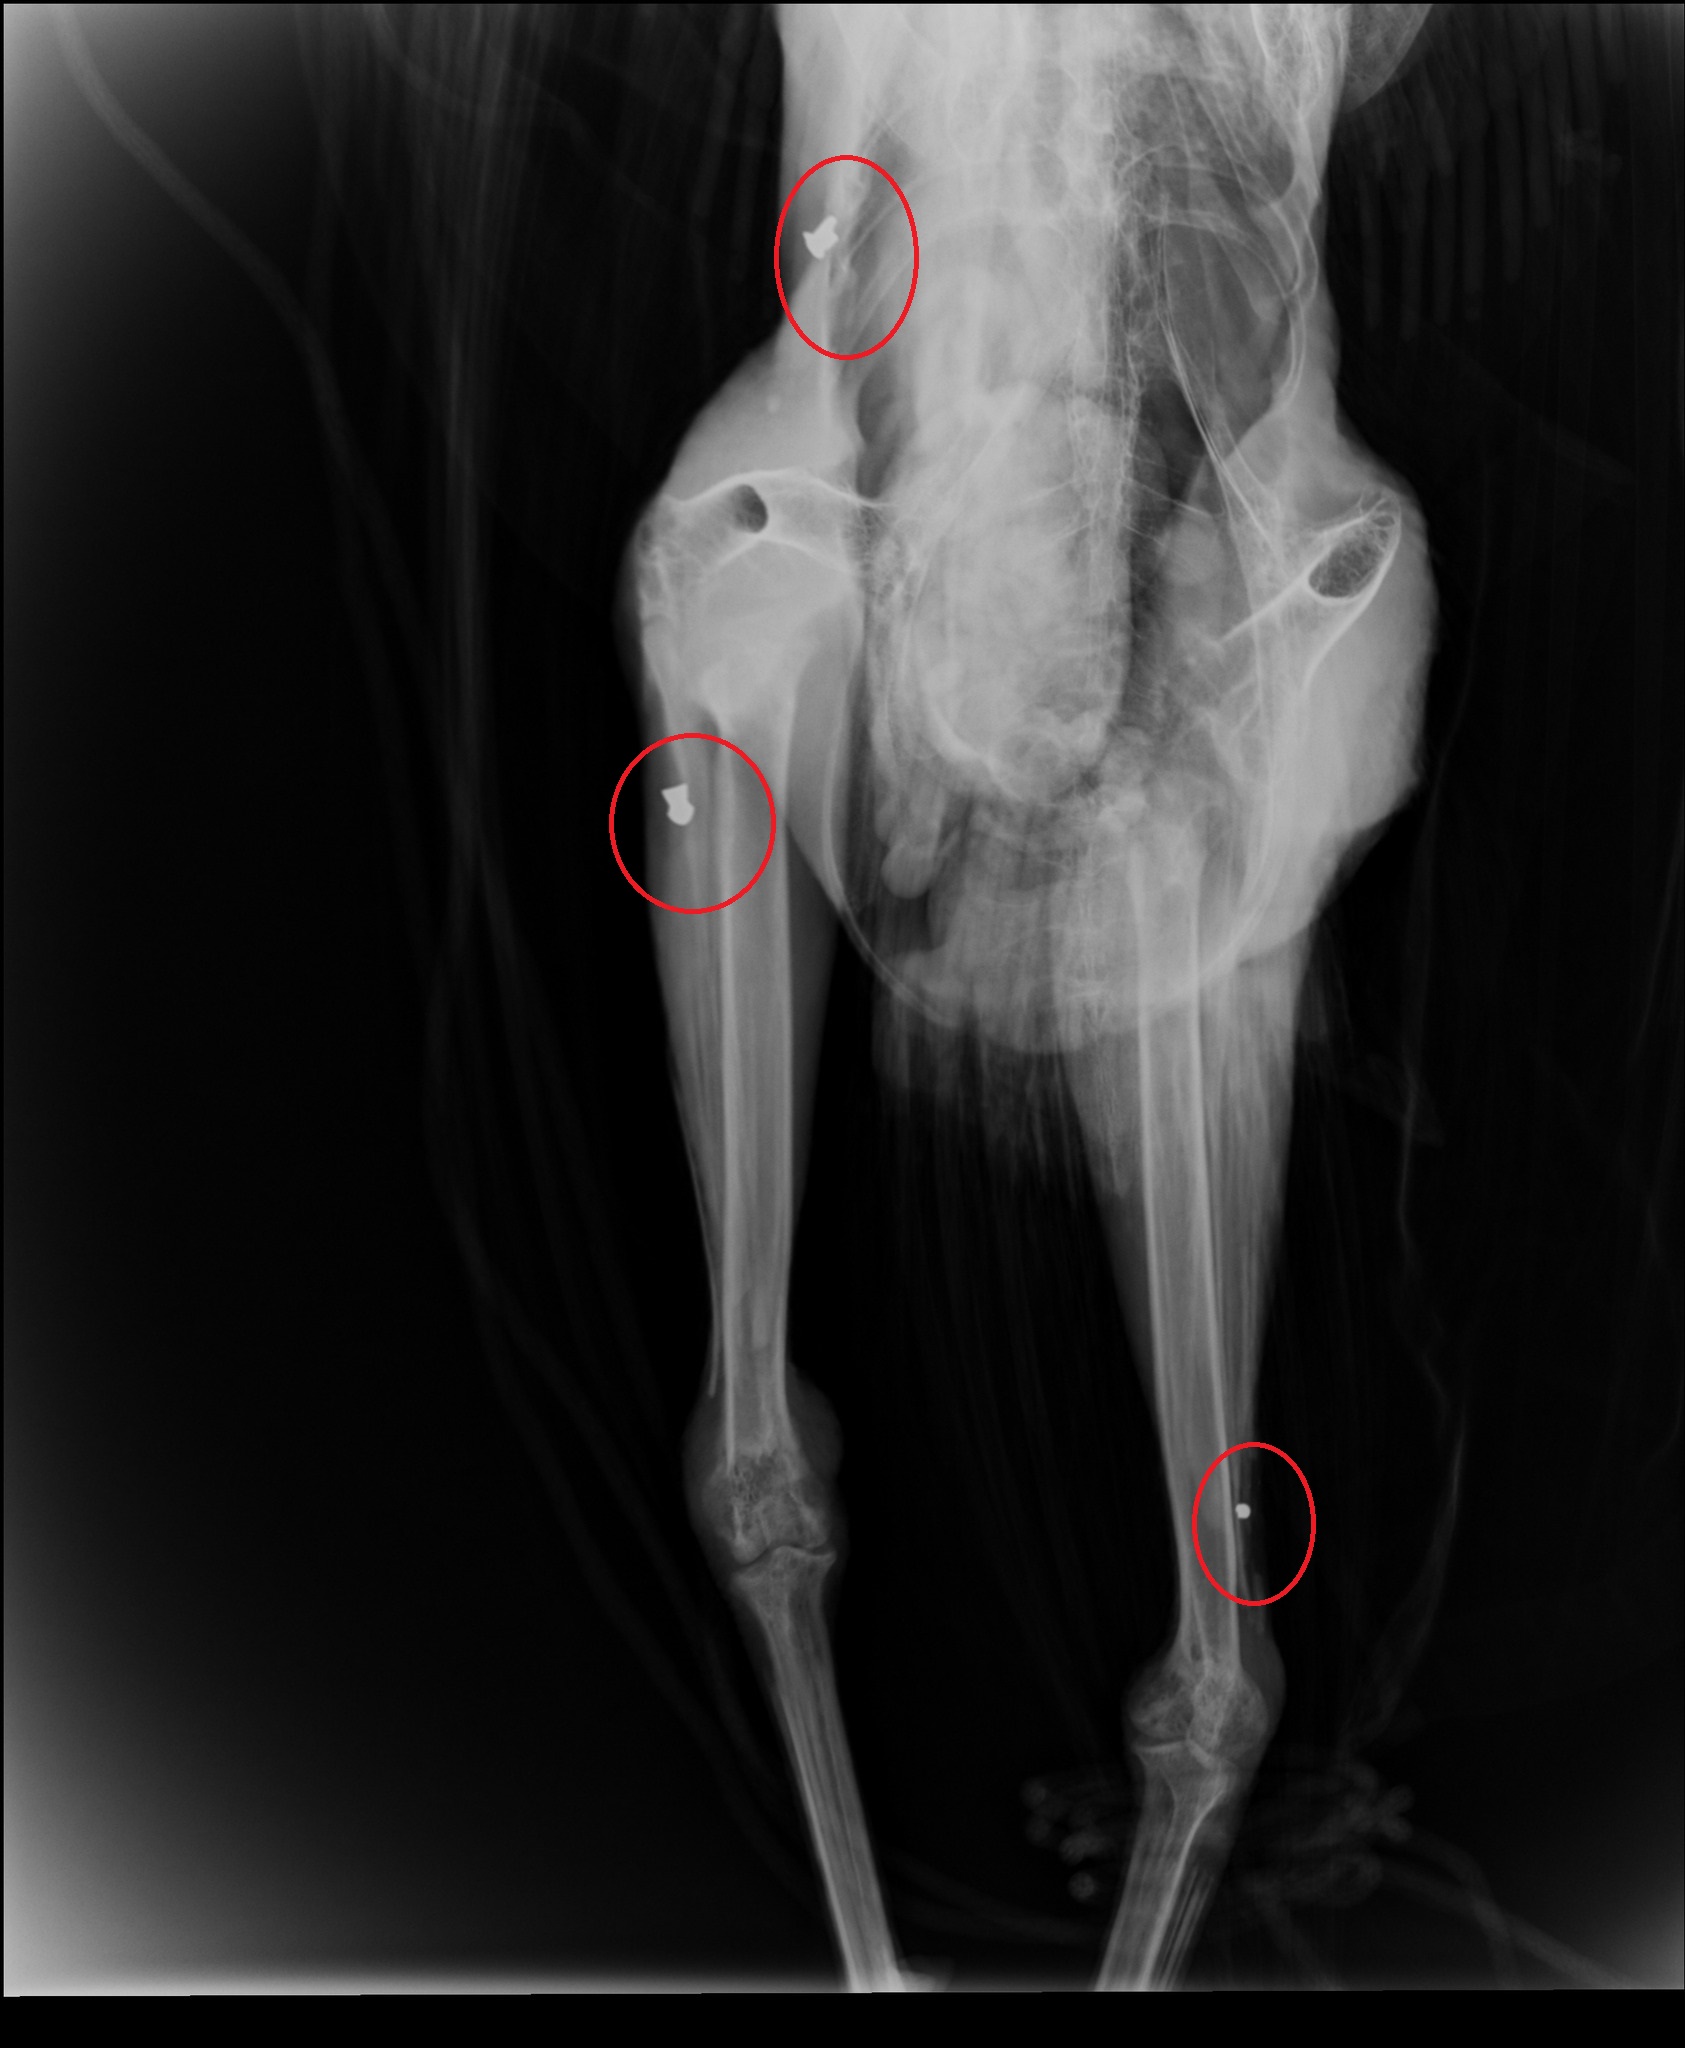

Το εντυπωσιακό πτηνό φέρεται να δέχθηκε πυροβολισμούς, γεγονός που επιβεβαίωσαν και σχετικές ακτινογραφίες που "έδειξαν" μάλιστα δυο βολίδες αεροβόλου κι ένα σκάγι.

Το παγώνι φέρεται να δέχθηκε πυροβολισμούς, γεγονός που επιβεβαίωσαν και σχετικές ακτινογραφίες που "έδειξαν" μάλιστα δυο βολίδες αεροβόλου κι ένα σκάγι.

"Το ζώο αυτό έχει πυροβοληθεί τρείς φορές, την ίδια ώρα ή διαφορετικές δεν μπορούμε να ξέρουμε, ούτε αν ο δράστης είναι ένας ή δύο ή τρεις, μέσα ή δίπλα σ έναν από τους πιο πολυσύχναστους αρχαιολογικούς χώρους της Κρήτης και της Ελλάδας γενικότερα" αναφέρει χαρακτηριστικά σε ανάρτηση του ο Σύλλογος ΑΝΙΜΑ.